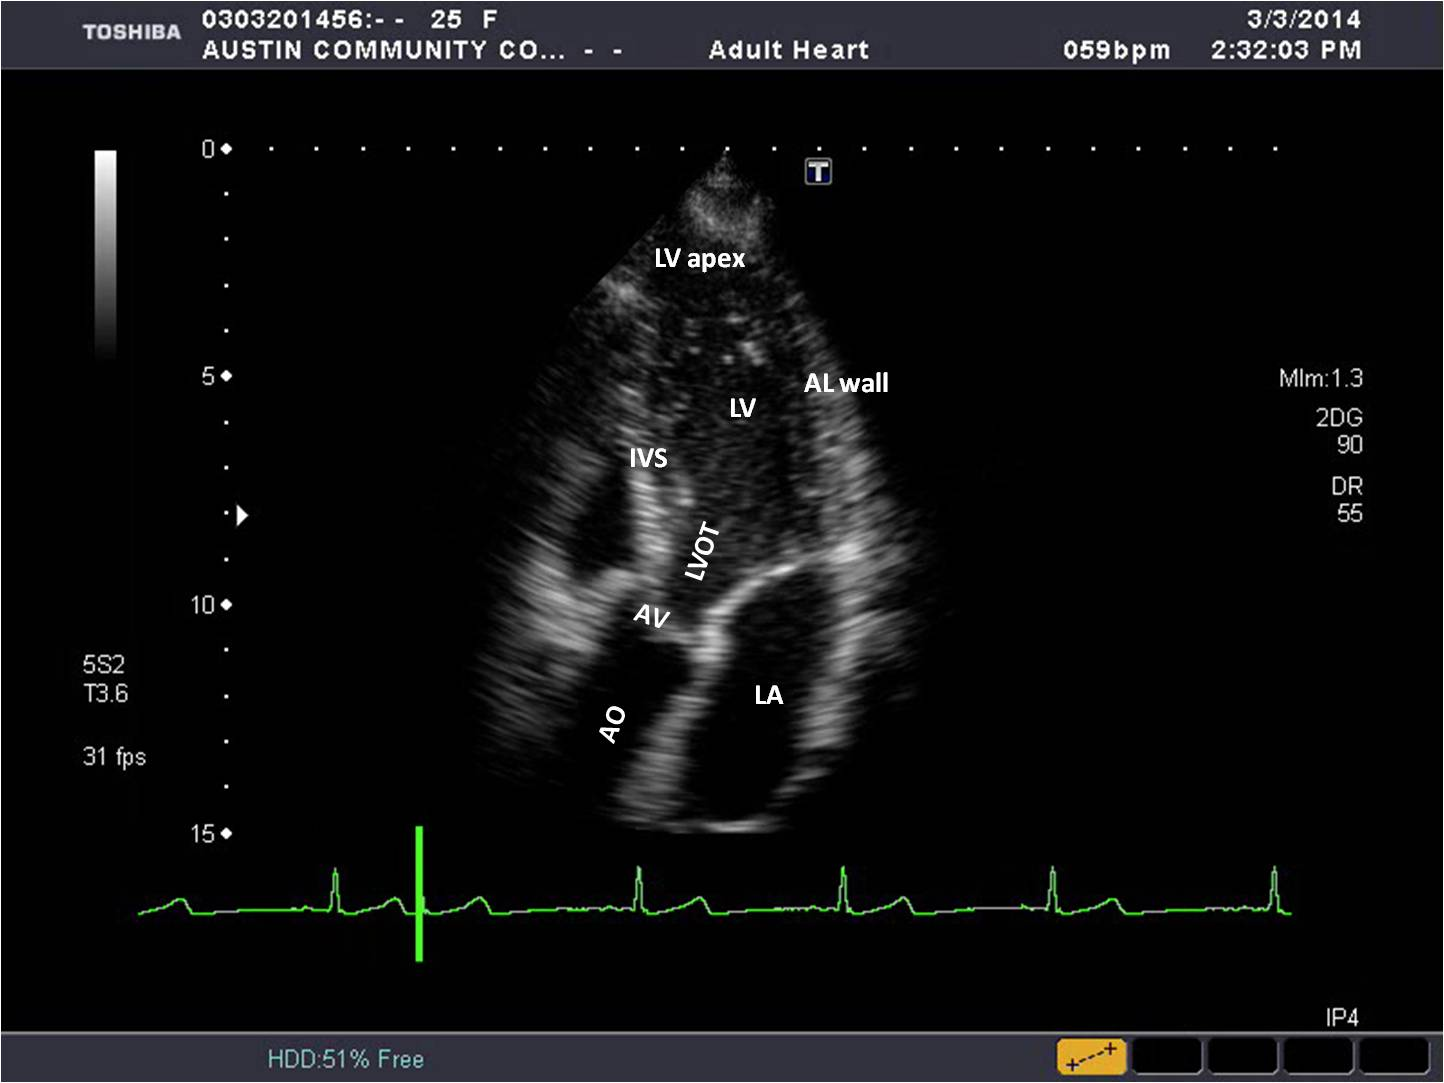

Draw and label the apical 3 chamber view.